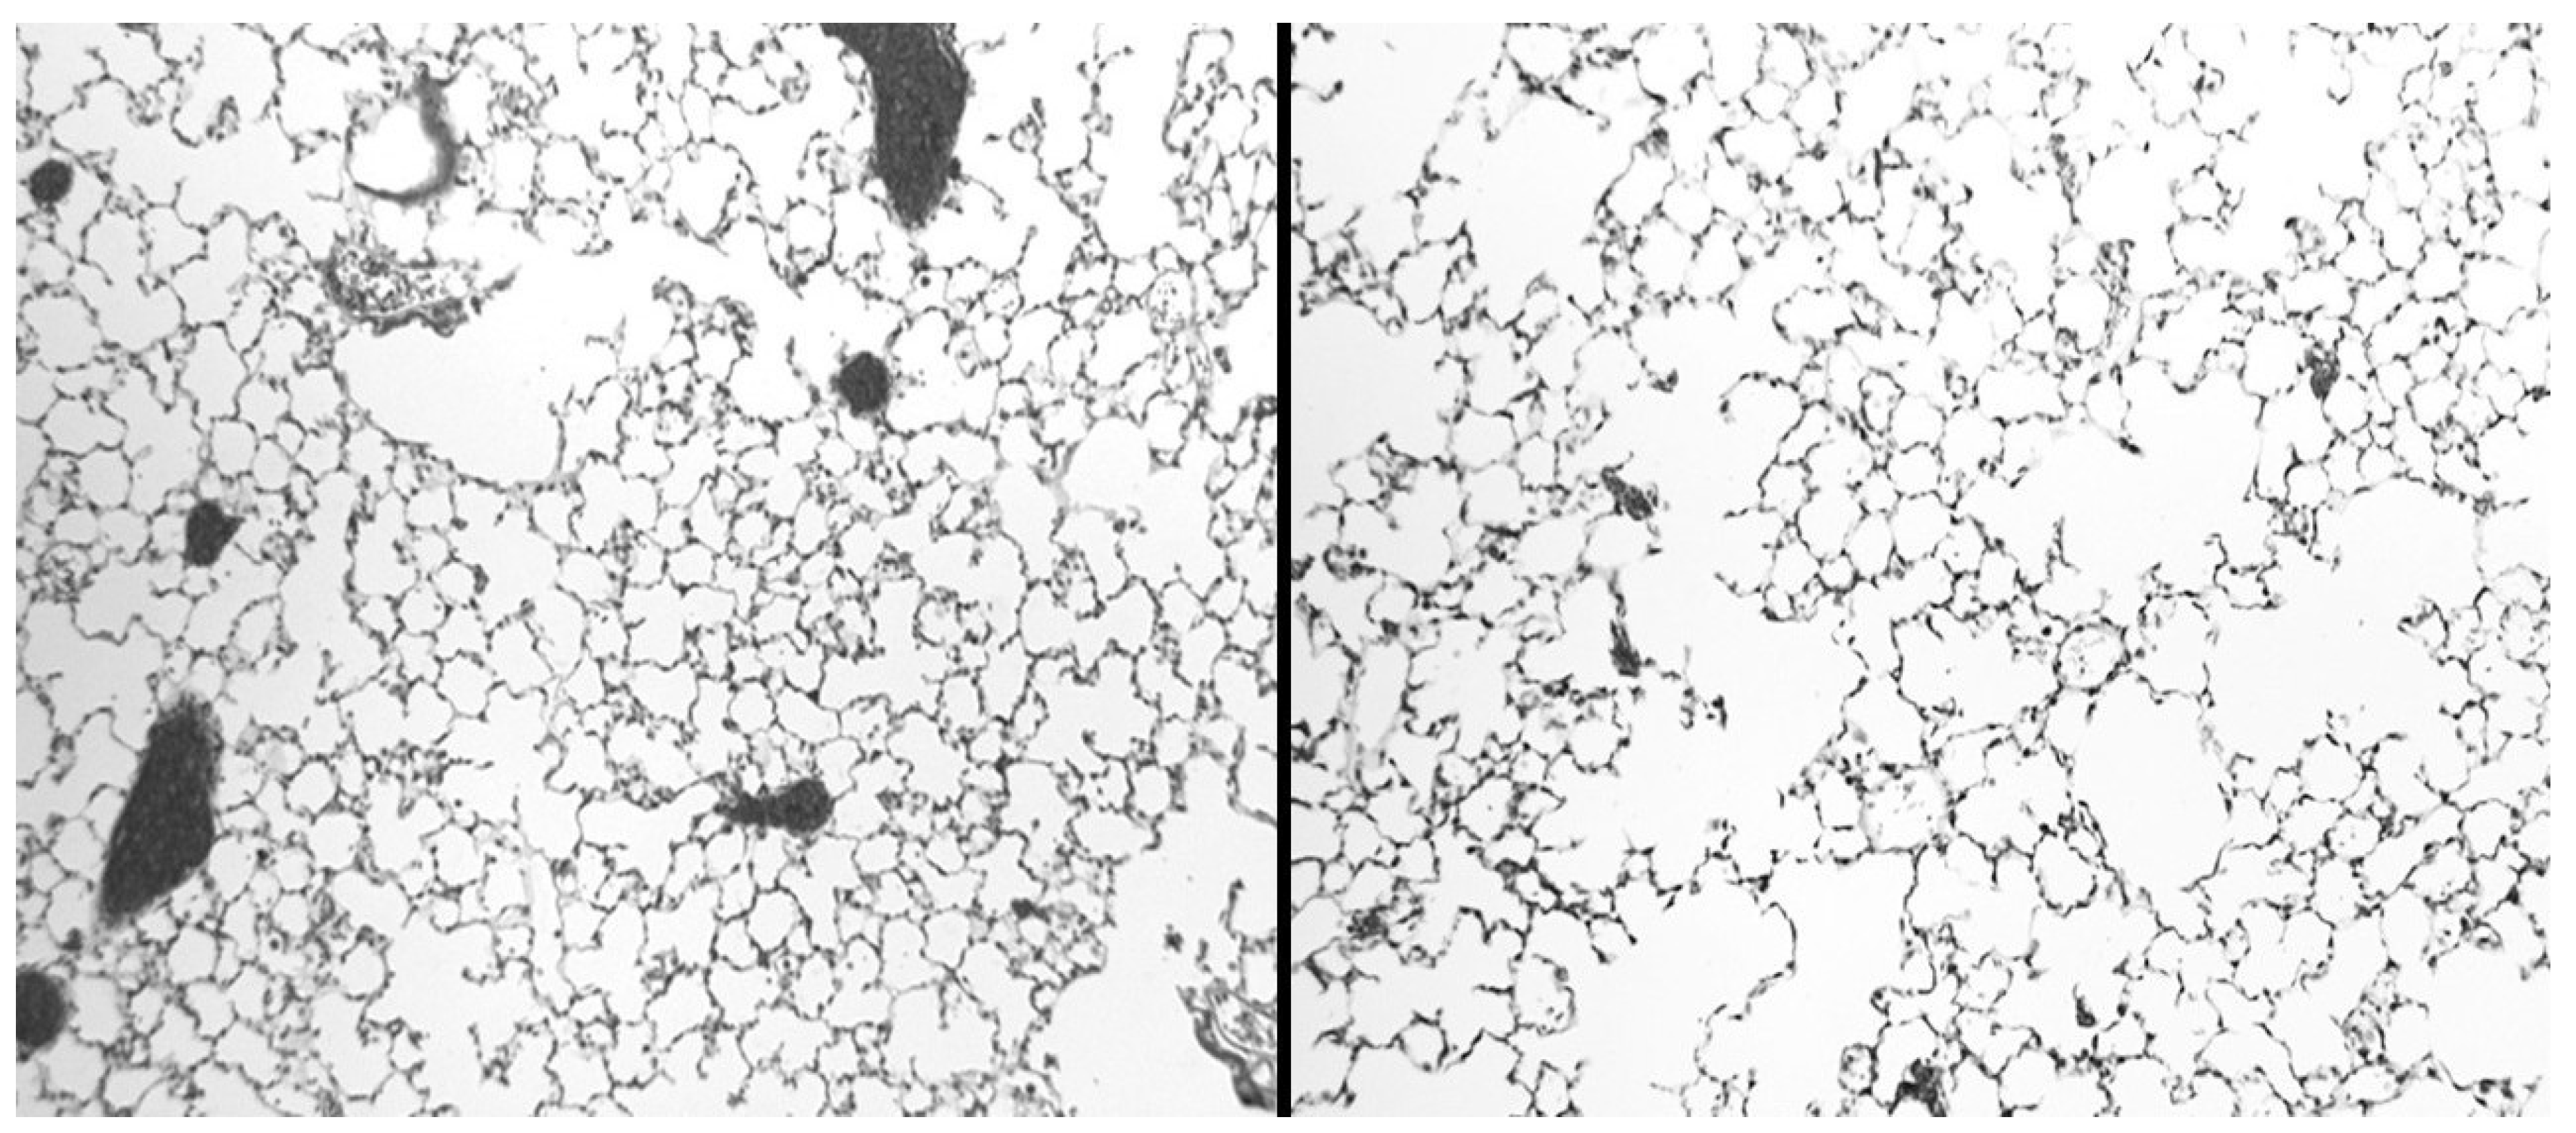

4.1. Biochemical and Morphological Features

- Cantor, J.O.; Cerreta, J.M.; Ochoa, M.; Ma, S.; Chow, T.; Grunig, G.; Turino, G.M. Aerosolized hyaluronan limits airspace enlargement in a mouse model of cigarette smoke–induced pulmonary emphysema. Experimental lung research 2005, 31(4), 417–430. [Google Scholar] [CrossRef]